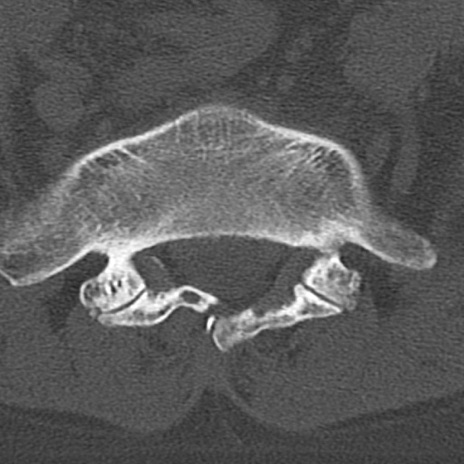

腰椎CT

横断像と矢状断像